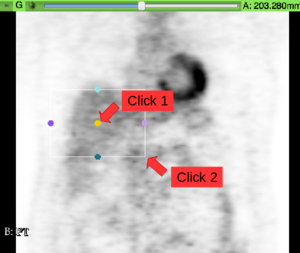

Screenshot

• Region: A ROI box may be provided to indicate the rough location of the liver. The tool will only search for a measurement region with its center inside of the provided ROI. Usage: (a) Select ROI from the annotation toolbar. (b) Place ROI around the liver by first clicking at the ROI’s center and then at a corner point. (c) From the “Region” drop-down list select the created ROI “R”.

Initialize ROI placement Place ROI around liver